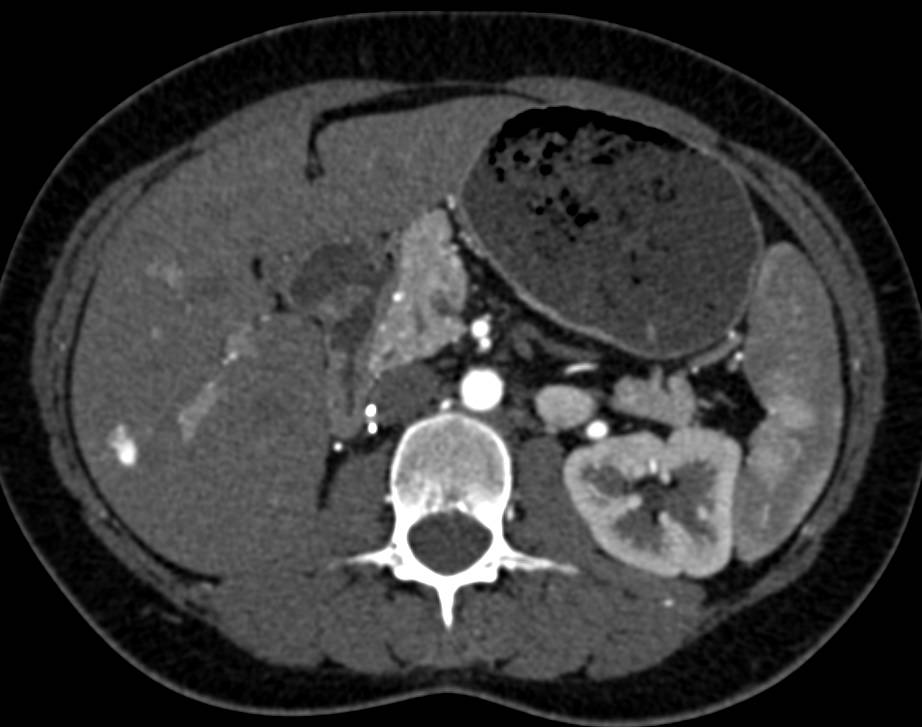

from www.ctisus.com

Flash Filling Hepatic Hemangiomas Liver Case Studies CTisus CT Scanning

Flash Filling Hemangioma Right Lobe of Liver Liver Case Studies What Is Flash Filling Hemangioma Find out more about this. hepatic hemangiomas or hepaticvenous malformations are the most common benign vascular liver lesions. a liver hemangioma is a noncancerous mass that typically doesn't need treatment. A liver hemangioma (hepatic hemangioma) is a noncancerous tumor in your liver. what is a liver hemangioma? What Is Flash Filling Hemangioma.